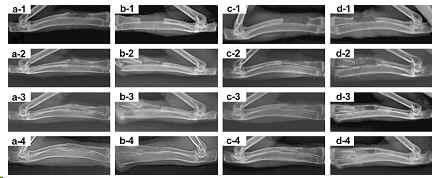

[Abstract]: Nanocomposite of hydroxyapatite (HAP) surface-grafted with poly(l-lactide) (PLLA) (g-HAP) shows a wide application for bone fixation materials due to its improved interface compatibility, mechanical property and biocompatibility in our previous study. In this paper, a 3-D porous scaffold of g-HAP/poly(lactide-co-glycolide) (PLGA) was fabricated using the solvent casting/particulate leaching method to investigate its applications in bone replacement and tissue engineering. The composite of un-grafted HAP/PLGA and neat PLGA were used as controls. Their in vivo mineralization and osteogenesis were investigated by intramuscular implantation and replacement for repairing radius defects of rabbits. After surface modification, more uniform distribution of g-HAP particles but a lower calcium exposure on the surface of g-HAP/PLGA was observed. Intramuscular implantation study showed that the scaffold of g-HAP/PLGA was more stable than that of PLGA, and exhibited similar mineralization and biodegradability to HAP/PLGA at the 12-20 weeks post-surgery. The implantation study for repairing critical radius defects showed that the scaffold of g-HAP/PLGA exhibited rapid and strong mineralization and osteoconductivity, and the incorporation of BMP-2 could enhance the osteogenic process of the composite implant. The new bone formation with the intact structure of a long bone was guided by the implant of g-HAP/PLGA.